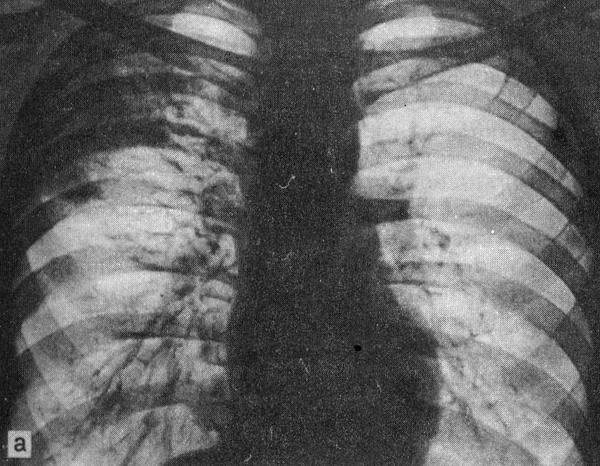

Иллюстрации по теме очагового и инфильтративного туберкулеза

Раздел: Фотодневник открытий